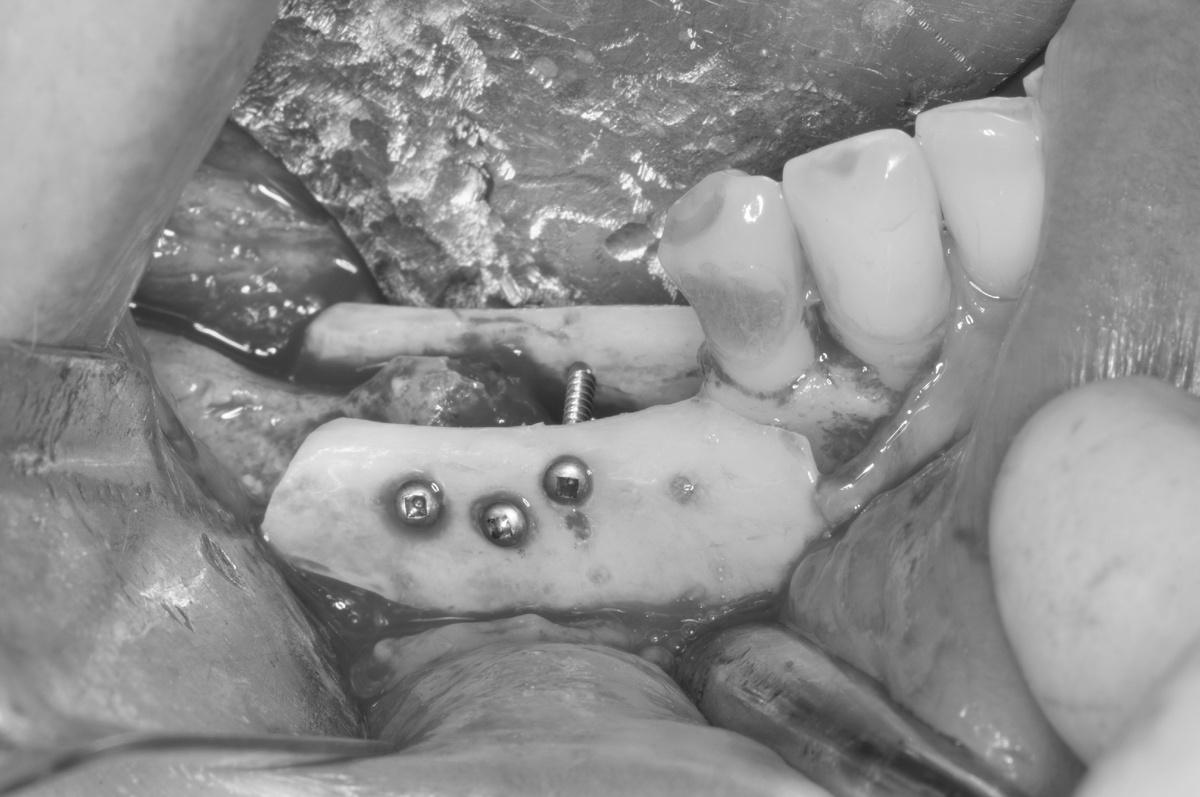

Нижняя челюсть

Справа проводим пластику кости по высоте и ширине специальной «каркасной» техникой остеопластики титановой сеткой (№3 на снимке ОПТГ), которую применяем при экстремальной атрофии костной ткани челюсти

Слева на нижней челюсти наращиваем костный объем с помощью костных блоков (№4 на снимке ОПТГ)

-

Остеопластика слева и справа была проведена за 1 визит

Операция длилась 6 часов, проводилась в седации

Костный материал — костные блоки, аутогенная костная стружка в сочетании с натуральным костнозамещающим материалом Bio-Oss

Остеопластика на нижней челюсти на снимке ОПТГ

Результат вживую: